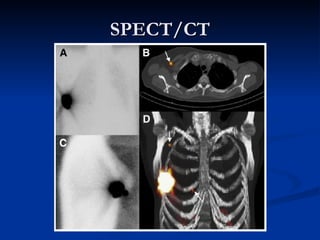

SPECT/CT